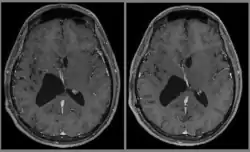

Le diagnostic est réalisé grâce à l'imagerie cérébrale, scanner ou au mieux IRM cérébrale, retrouvant cette formation hétérogène à trois composantes en général (tissulaire +/- kystique et calcique), avec rehaussement partiel à l'injection de produit de contraste.

Elle permet d'étudier les rapports avec les zones fonctionnelles du cerveau (notamment le pilier du fornix, un des composants du circuit de Papez responsable de la mémoire antérograde), le système vasculaire (réseau veineux profond), ainsi que le retentissement de la tumeur sur le cerveau (effet de masse de par l'hydrocéphalie, œdème, hémorragie, engagement…).